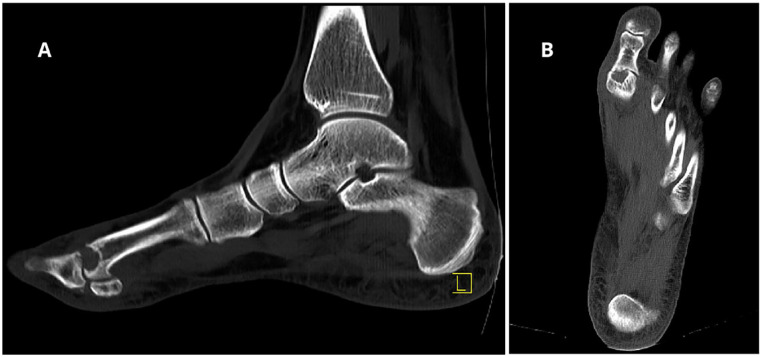

Methods: We report the case of a 43-year-old woman with persistent pain and functional limitations after a failed PVA hydrogel implant in the first MTP joint. The revision surgery involved a biologic resurfacing using the Osteochondral Autograft Transfer System (OATS) with a graft harvested from the ipsilateral femoral condyle, complemented by interpositional arthroplasty with a dermal graft and a proximal phalanx closing wedge osteotomy to correct residual hallux valgus.

Results: At the 3-year follow-up, the patient-reported complete resolution of pain and returned to full activity with improved range of motion (40 degrees dorsiflexion, 15 degrees plantarflexion). Radiographic evaluation demonstrated graft incorporation and restoration of joint space, confirming the success of the procedure.